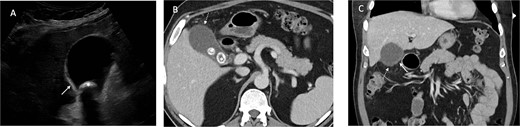

Urgent ultrasound of the upper abdomen and CT abdomen and pelvis were requested. US revealed multiple gallbladder calculi and a 15 mm non-mobile calculus in the neck, and asymmetric thickening of the gallbladder wall suggestive of chronic calculous cholecystitis (Fig. 1). CT showed

Ultrasound demonstrates gallbladder wall thickening (solid white arrow in A) and gallstone (* in A). Contrast enhanced CT of the abdomen in portal venous phase axial (B) and coronal (C) planes demonstrate gallbladder wall thickening (solid white arrow in C) and area of nonenhancing wall (dashed white arrow in B and C) and gallstones (* in B).